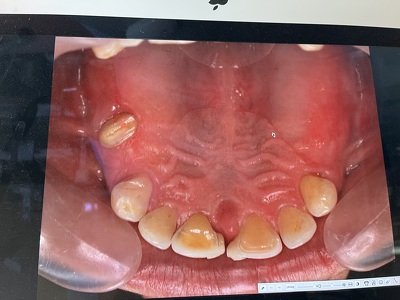

初診より8年後の上顎の写真。初診時の写真は不明。